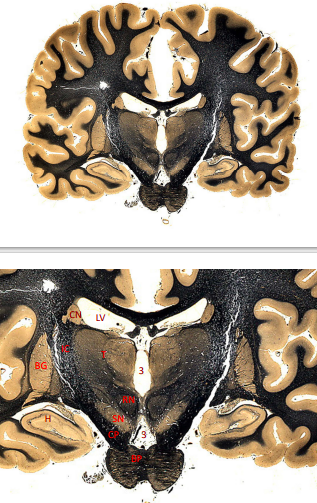

label, note important features